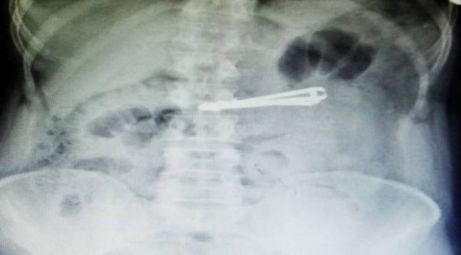

Tırnak makasını yuttu!